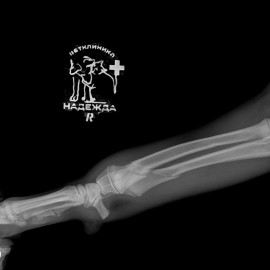

Наш пациент после автотравмы. После осмотра и проведения рентгенологических исследований выл поставлен диагноз - косой диафизарный перелом правой лучевой и локтевой кости со смещением. Была проведена операция - остеосинтез костей правого предплечья.

Снимки до операции.